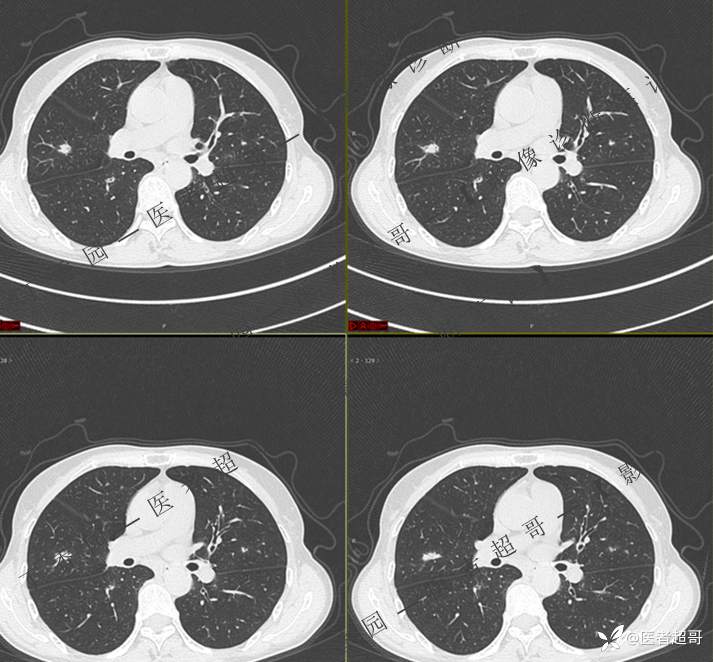

第一次检查